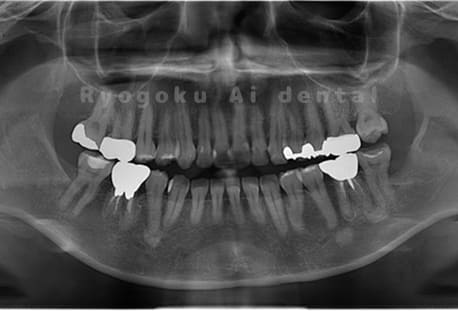

Case02

-

- 原因

- 下顎の水平埋伏智歯

- 治療内容

- 下顎の水平埋伏智歯を抜歯

<リスク・副作用>

手術後は痛み、腫れ、痺れなどの副作用が生じる場合があります。